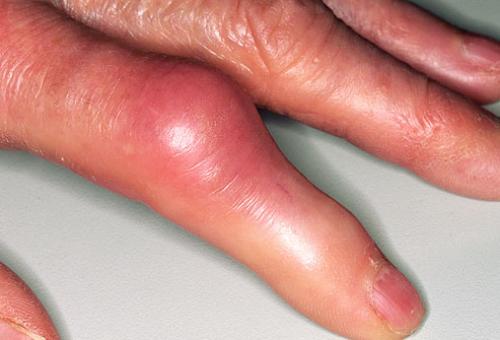

Фото: подагрический артрит

Фото: подагра суставов рук

Фото: тофус при подагре

Приступ начинается внезапно с острой боли в суставе, чаще всего большого пальца. Обычно это происходит ночью, боль настолько сильная, что к больному месту невозможно прикоснуться, появляется отек сустава, кожа над ним темнеет. Наиболее часто появляется шишка на большом пальце руки. Наросты, возникающие при, называются тофусы. Они представляют собой скопление кристаллов мочевой кислоты. Приступ длится от 3 до 10 дней, потом проходит. Через какое-то время приступ повторяется.